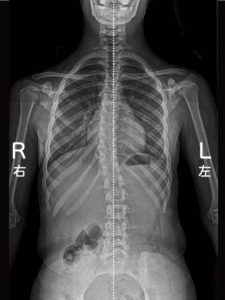

定義:正面(冠状面)で脊柱が側方へ弯曲。多くは**特発性(原因不明)**で、学童期〜思春期に発見されやすい。

冠状面:側方弯曲

矢状面:胸椎後弯/腰椎前弯の乱れ

回旋:胸郭のリブハンプ(前屈で顕著)として現れる

Cobb角:終椎(上端・下端椎)の終板に引いた接線の交角。

学校検診:視診・前屈テスト(リブハンプ)・モアレ法→疑い例はX線で確定診断。